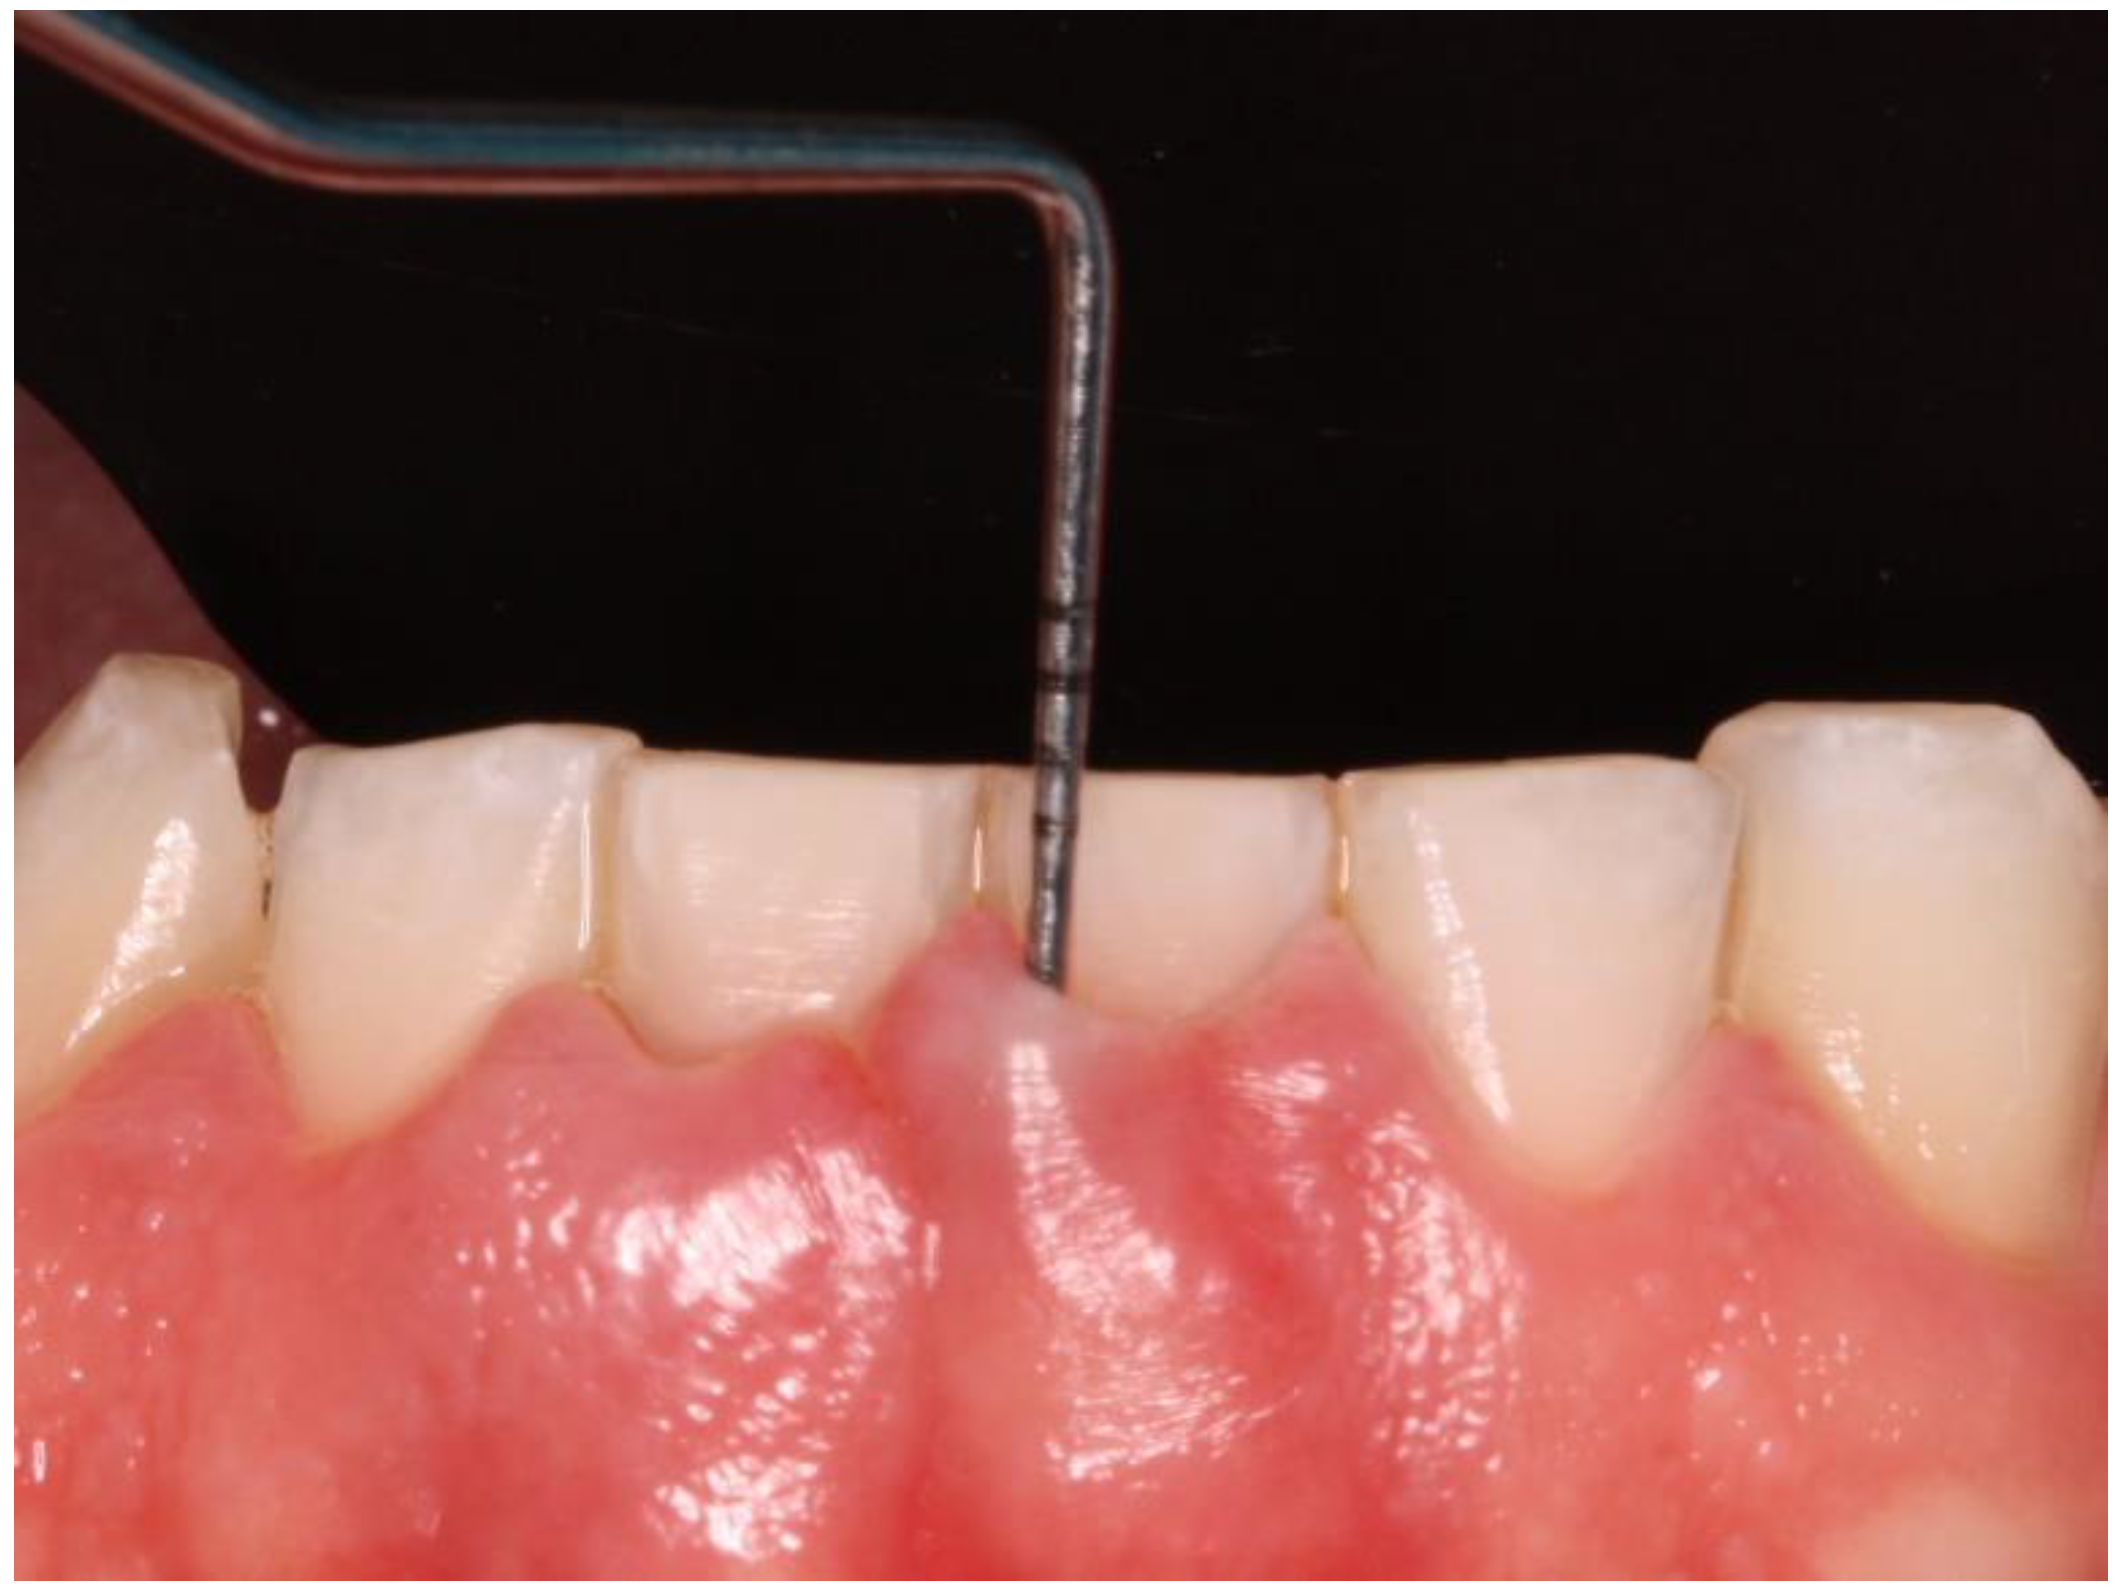

Clinical data of all teeth, excluding third molars, were obtained during oral examinations at initial visits. Accredited Oral Hygienists and Dentists performed whole-mouth oral examinations. The manual periodontal probe PCPUNC15 was used for oral examinations. Oral examinations included periodontal pocket depth (PPD; 6 sites per tooth) (Figure 1) and bleeding on probing (GBI; 4 sites per tooth).[23]

Figure 1. Periodontal probing.